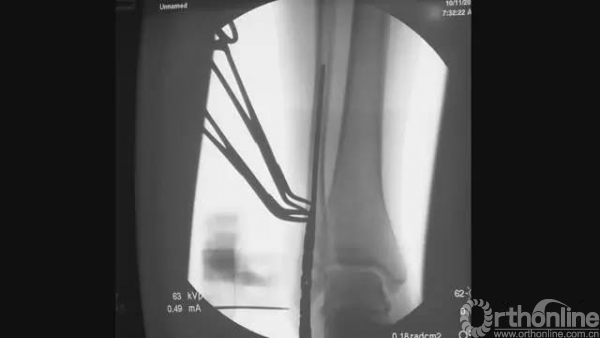

扩髓完成后,将髓内钉插入

正侧位透视,髓内钉位置满意

行远端锁钉

行下胫腓联合锁钉

拧入适合长度的锁钉